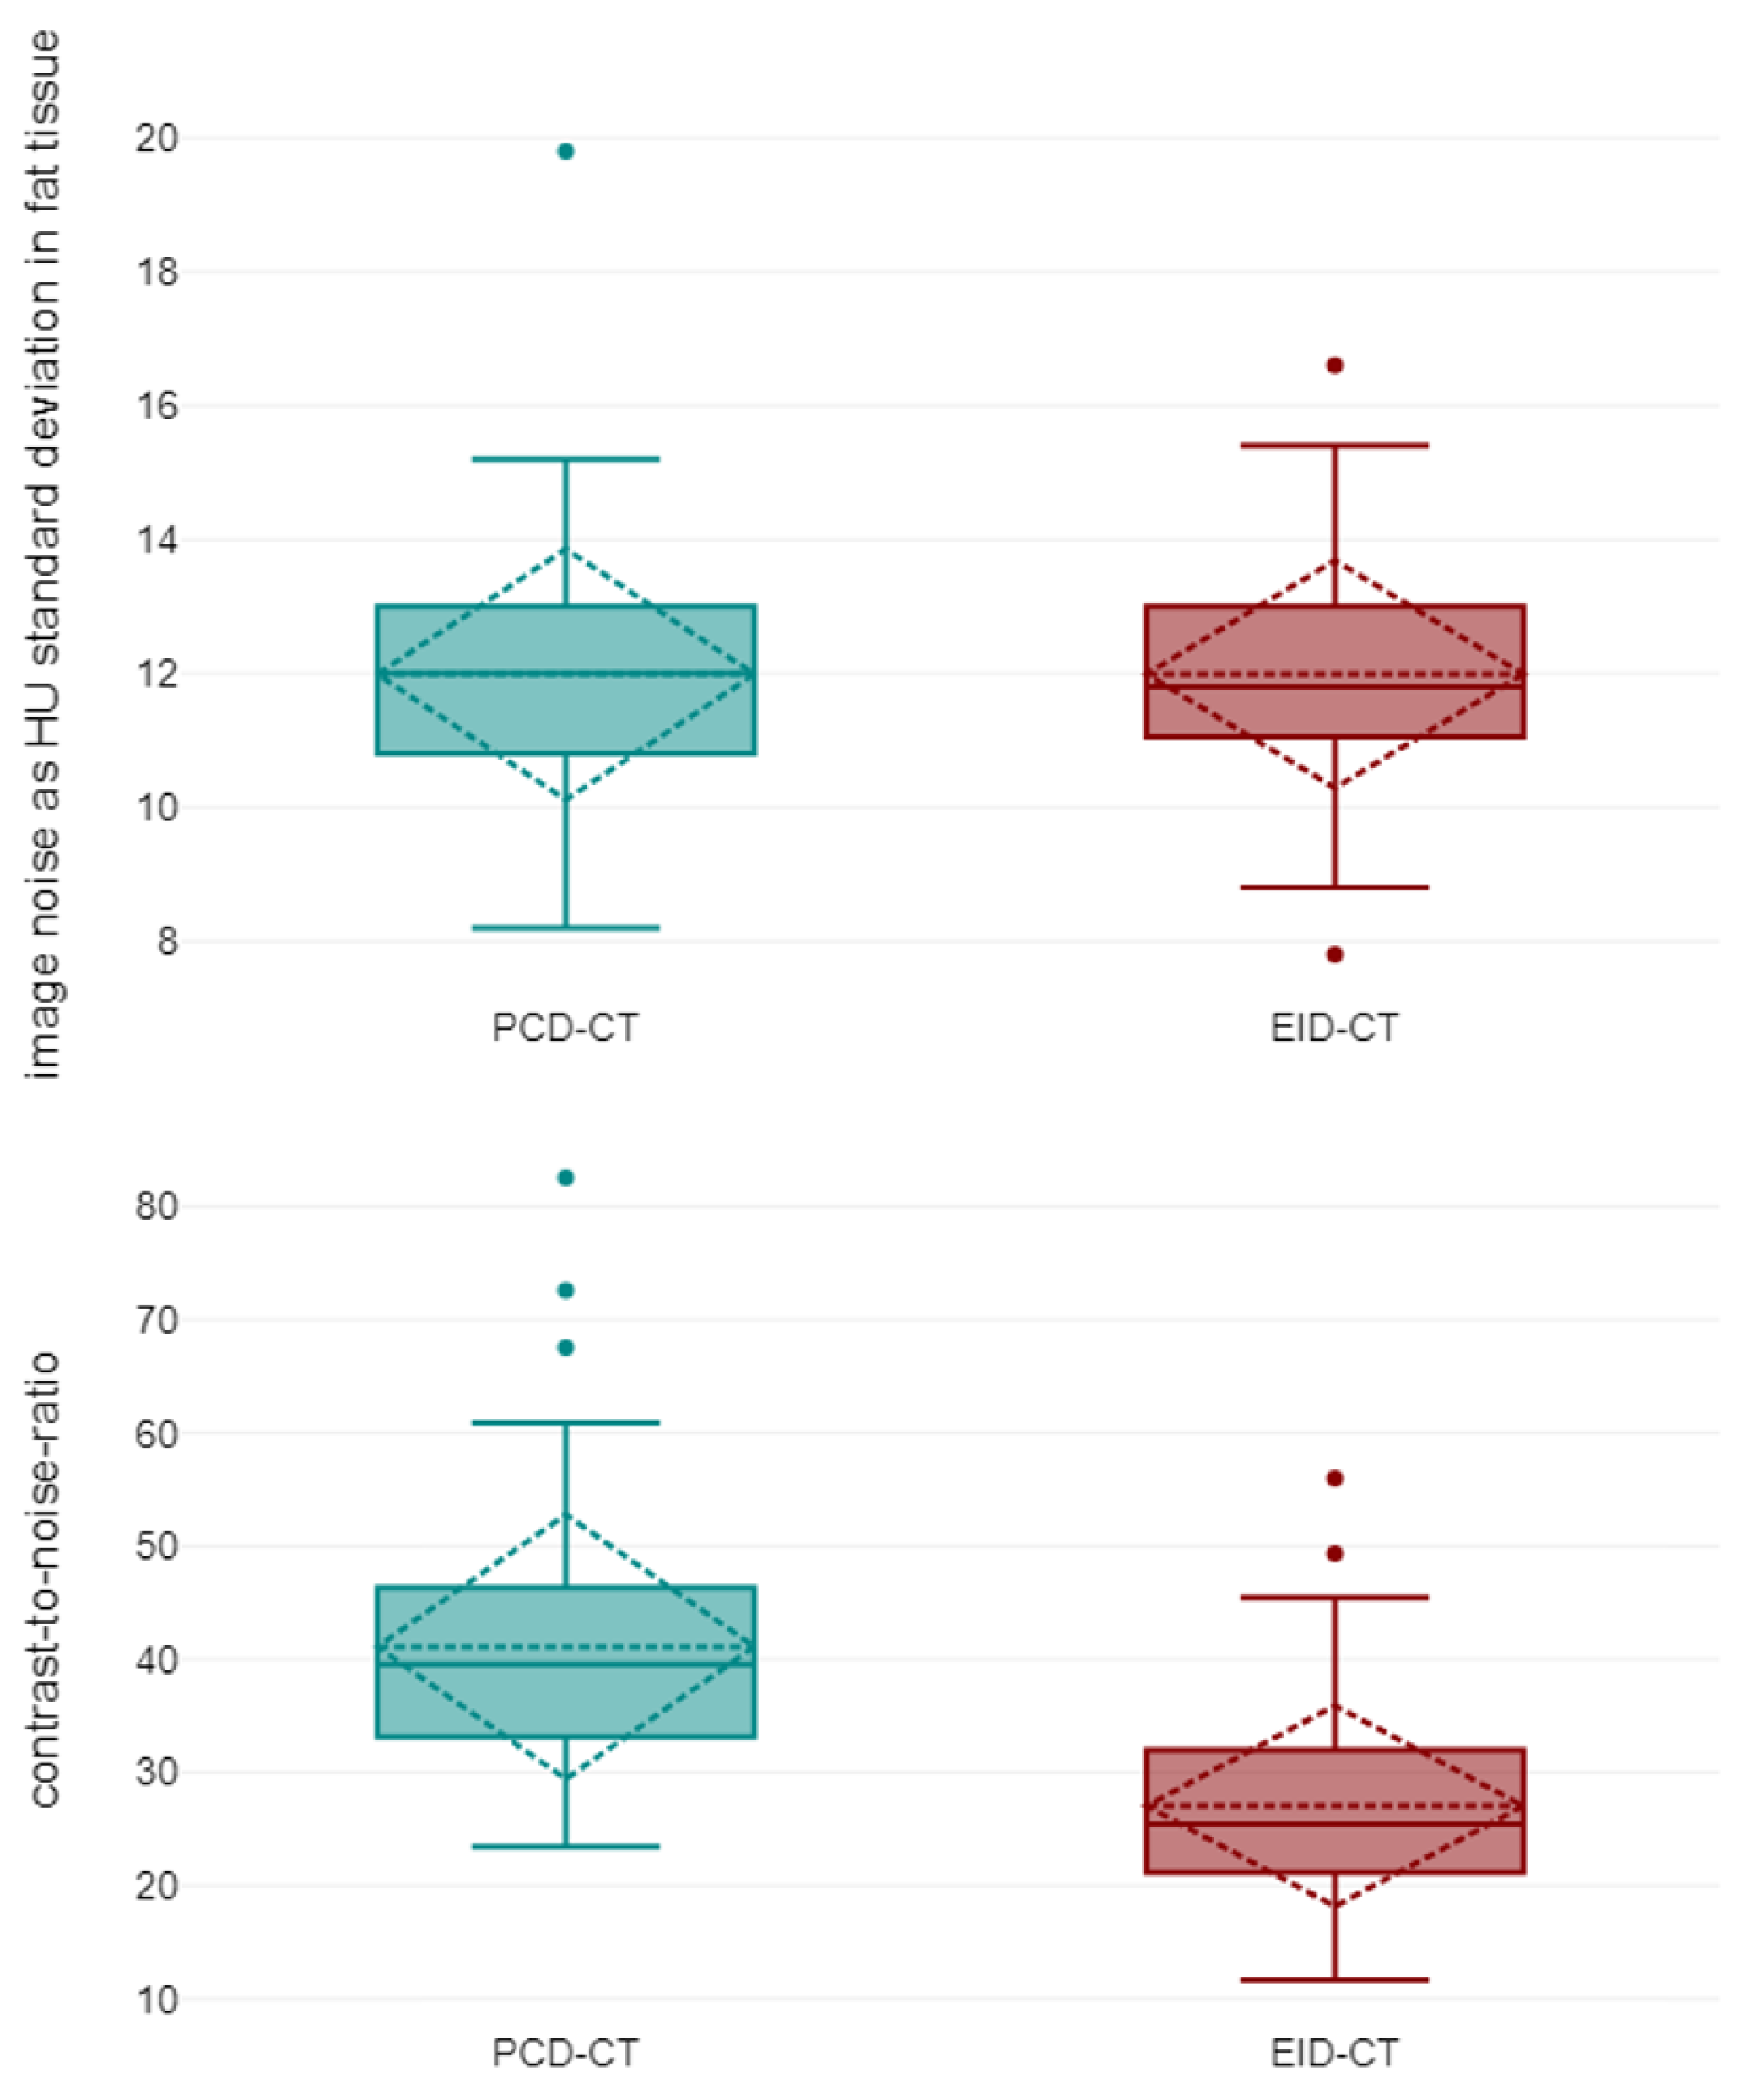

3.2. Objective Image Quality